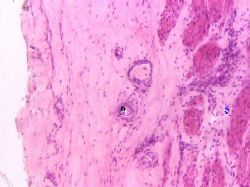

| 2. а) Мышечная оболочка (5) образована пучками гладких

миоцитов. б) В этой

оболочке

до середины

мочеточников - 2 слоя,

а ниже - 3

слоя.

в) Клетки в слоях расположены спиралевидно -

с противоположным (в соседних

слоях) ходом спирали.

3. Наружная

оболочка (6) является адвентициальной, т.е образована

только рыхлой соединительной тканью.

4. В стенке

мочеточников, как обычно, содержатся также

кровеносные

и лимфатические сосуды,

нервные окончания

(чувствительные и эфферентные),

интрамуральные ганглии и отдельные нейроны.